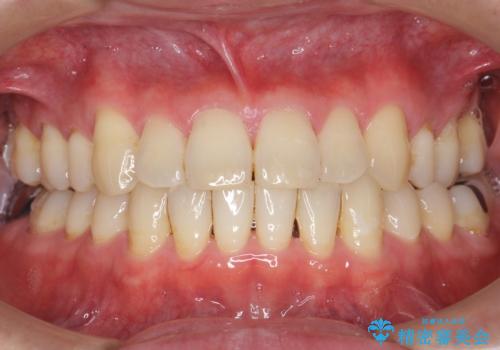

不適合な銀の詰め物とう蝕の除去により奥歯の違和感がなくなり、セラミック治療により機能性・審美性が向上し、患者様に喜んで頂けました。

被せ物の種類:右下6 e-max press セラミックインレー

右下7 メタルボンドクラウン エコノミー